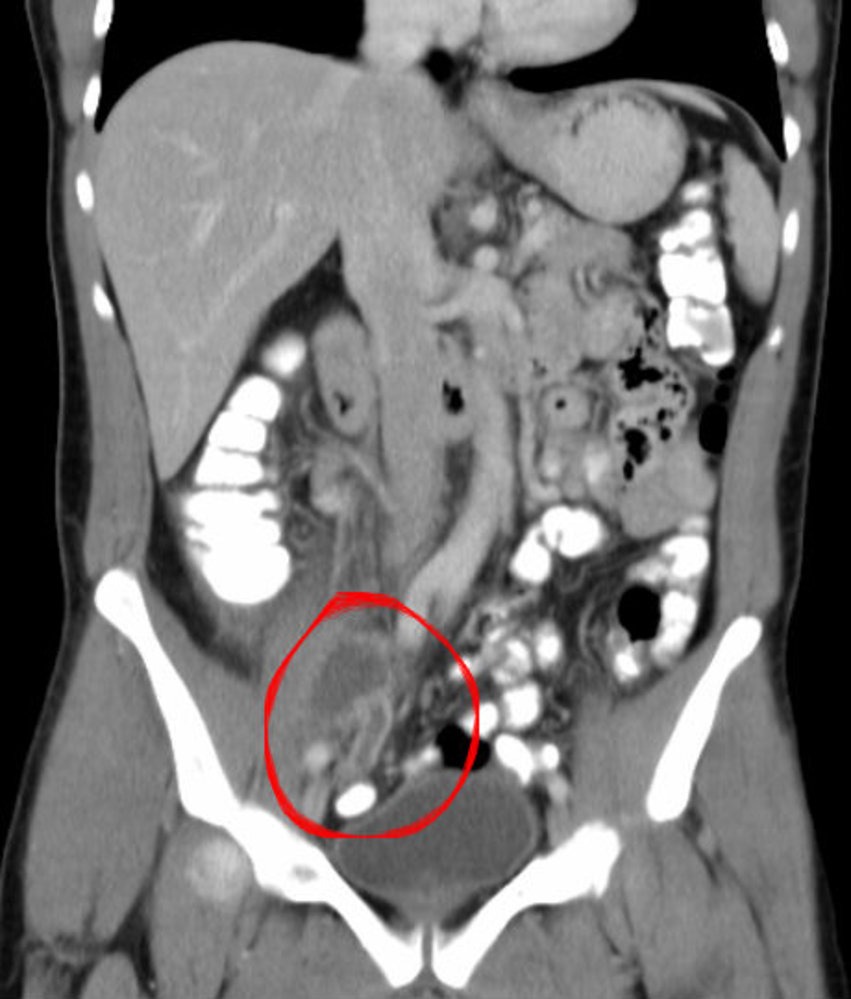

- CT Abdomen/Pelvis (with contrast): Gold standard in adults

- Appendix >6 mm, wall thickening, fat stranding, ± appendicolith